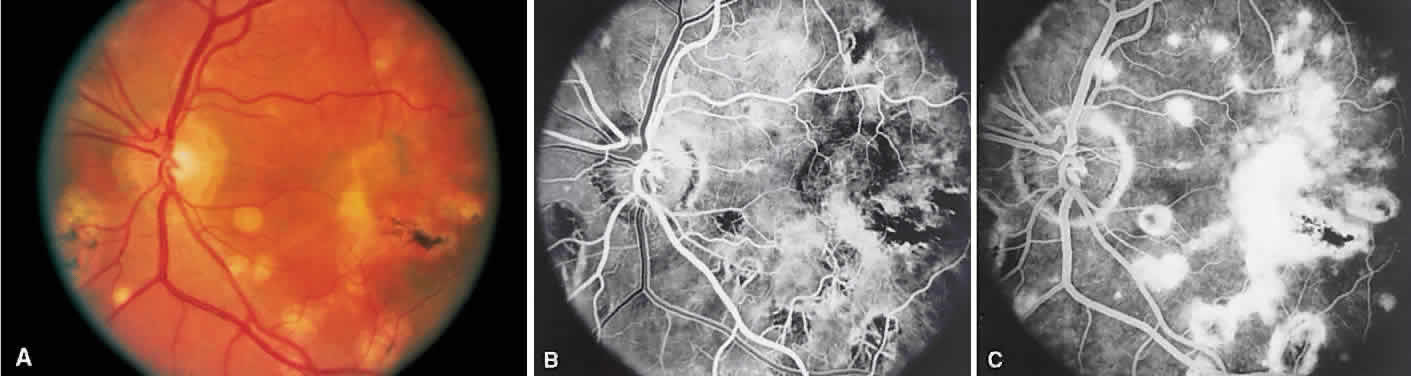

Multifocal choroiditis may mimic the typical clinical findings of presumed ocular histoplasmosis syndrome (discussed later) and has the additional finding of anterior chamber and vitreous cells. Multiple yellow or gray acute choroidal lesions measuring 50 to 350 μm, periphlebitis, and occasionally retinal neovascularization can be seen. Marked pigmentary disturbances may be seen in the chronic phase (Fig. 11A).

Fig. 11. Multifocal choroiditis. A. Fundus photograph showing pigmentary disturbances. B. Multiple areas of hypofluorescence and hyperfluorescence representing chorioretinal scars with associated atrophic areas. C. Indocyanine green angiogram shows multiple areas of hypofluorescence around the disc, the macula, and the midperipheral fundus. Some of these areas are not visible clinically or on fluorescein angiogram.

On fluorescein angiography (see Fig. 11B), the punched-out lesions show the typical window defects. Acute lesions block early choroidal fluorescence and stain late. Cystoid macular edema and prolonged arteriovenous circulation times may be seen.39 Progressive subretinal fibrosis is a reported sequela that presents as multiple stellar zones of subretinal fibrosis. This fibrosis can be surrounded by multiple atrophic punched-out lesions (Fig. 12).40

Fig. 12. Multifocal choroiditis with subretinal fibrosis in a 26-year-old woman. A and B. Color photographs show hypopigmented lesions representing subretinal fibrosis involving both macular lesions. Multiple punched-out lesions surround the bands of fibrosis. C. Staining of the large stellate fibrous lesion can be seen in the left macula. There are multiple punched-out lesions above and below the macular zone. Leakage from the optic disc and its vessels can also be seen.

ICG angiography shows large hypofluorescent spots in the posterior pole measuring 200 to 500 μm, which did not usually correspond to clinically or fluorescein angiographically detectable lesions (see Fig. 11C). Smaller hypofluorescent spots, less than 50 μm, also may be seen in the posterior pole. Both large and small lesions are best seen in the later phases of the angiogram. Confluent hypofluorescent areas may be seen around the optic nerve in patients reporting an enlarged blind spot on visual field testing.41